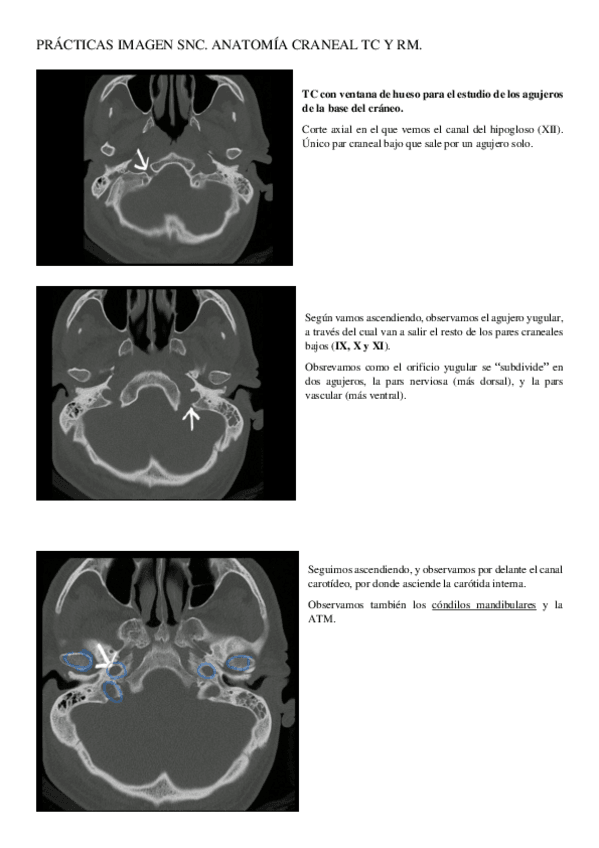

PRACTICAS-IMAGEN-SNC.pdf